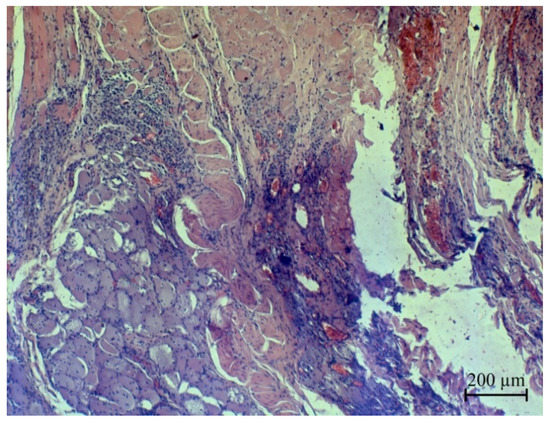

3.4. Investigation of Ag NPs and the Oxidized Ag NPs as a Covering Component of Suture Materials

- Rzhepakovsky, I.; Siddiqui, S.A.; Avanesyan, S.; Benlidayi, M.; Dhingra, K.; Dolgalev, A.; Enukashvily, N.; Fritsch, T.; Heinz, V.; Kochergin, S.; et al. Anti-arthritic effect of chicken embryo tissue hydrolyzate against adjuvant arthritis in rats (X-ray microtomographic and histopathological analysis). Food Sci. Nutr. 2021, 9, 5648–5669. [Google Scholar] [CrossRef]